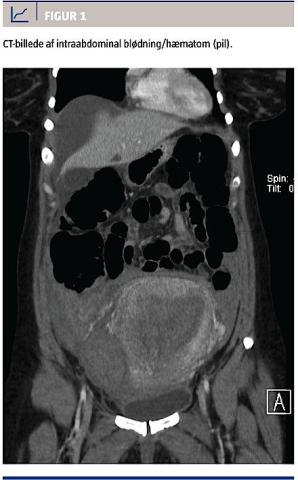

Tolv timer efter fødslen fik kvinden kraftige smerter fra epigastriet og diffust i nedre abdomen. Blodtrykket var 156/102 mmHg og pulsen 70 slag/min. Symptomerne blev tolket som efterveer, og tilstanden blev set an. Efter yderligere 12 timer blev den vagthavende læge tilkaldt pga. fortsat kraftige smerter. Kvinden var nu klinisk påvirket med et blodtryk på 80/50 mmHg og en puls 110 slag/min. En transabdominal ultralydskanning gav ikke mistanke om igangværende blødning, og mængden af vaginal blødning var tilladelig. Blodtrykket rettede sig hurtig med væskebehandling, men smerterne forværredes over de næste timer. Hæmoglobinniveauet var faldet fra 7,2 til 3,8 mmol/l. På mistanke om intraabdominal blødning blev der udført CT af abdomen, hvorved man fandt store mængder fri væske, specielt i højre side af abdomen, samt pleuraekssudat (Figur 1).